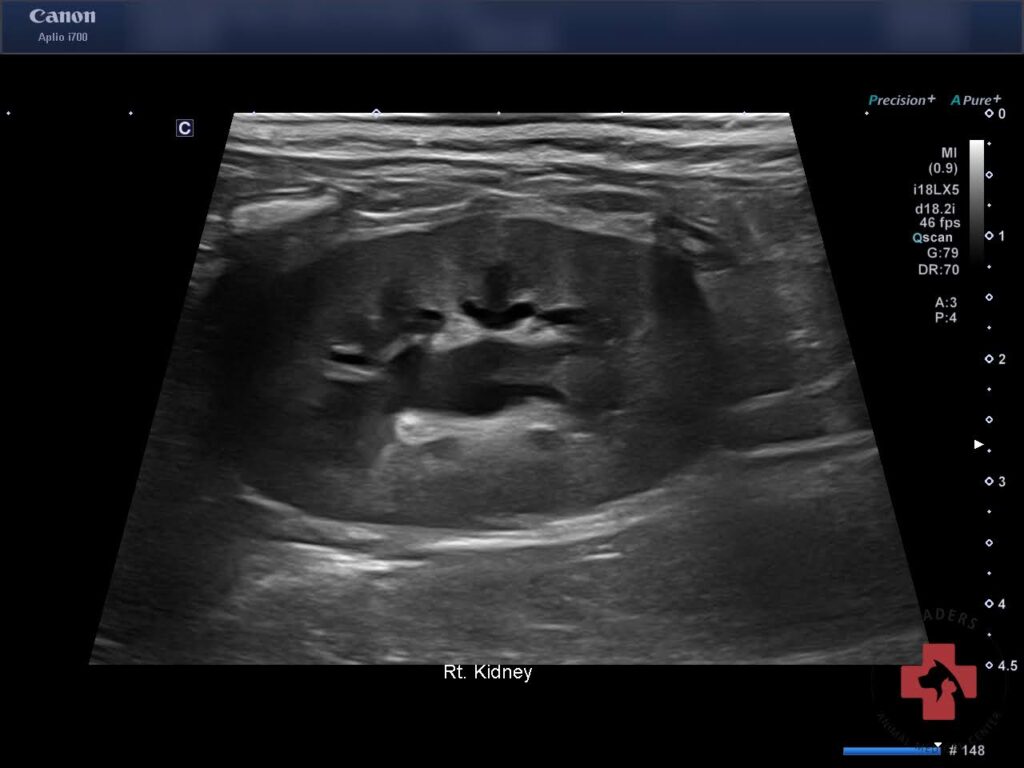

이후 실시한 본원 초음파 검사에서 양측 신장 주위 복막염 신장 피질 비후 양측 신장 신우 확장이 동반된 급성 신부전 변화가 확인되었습니다.

내원 당시 초음파검사(우측) / 출처: 동탄리더스동물의료원